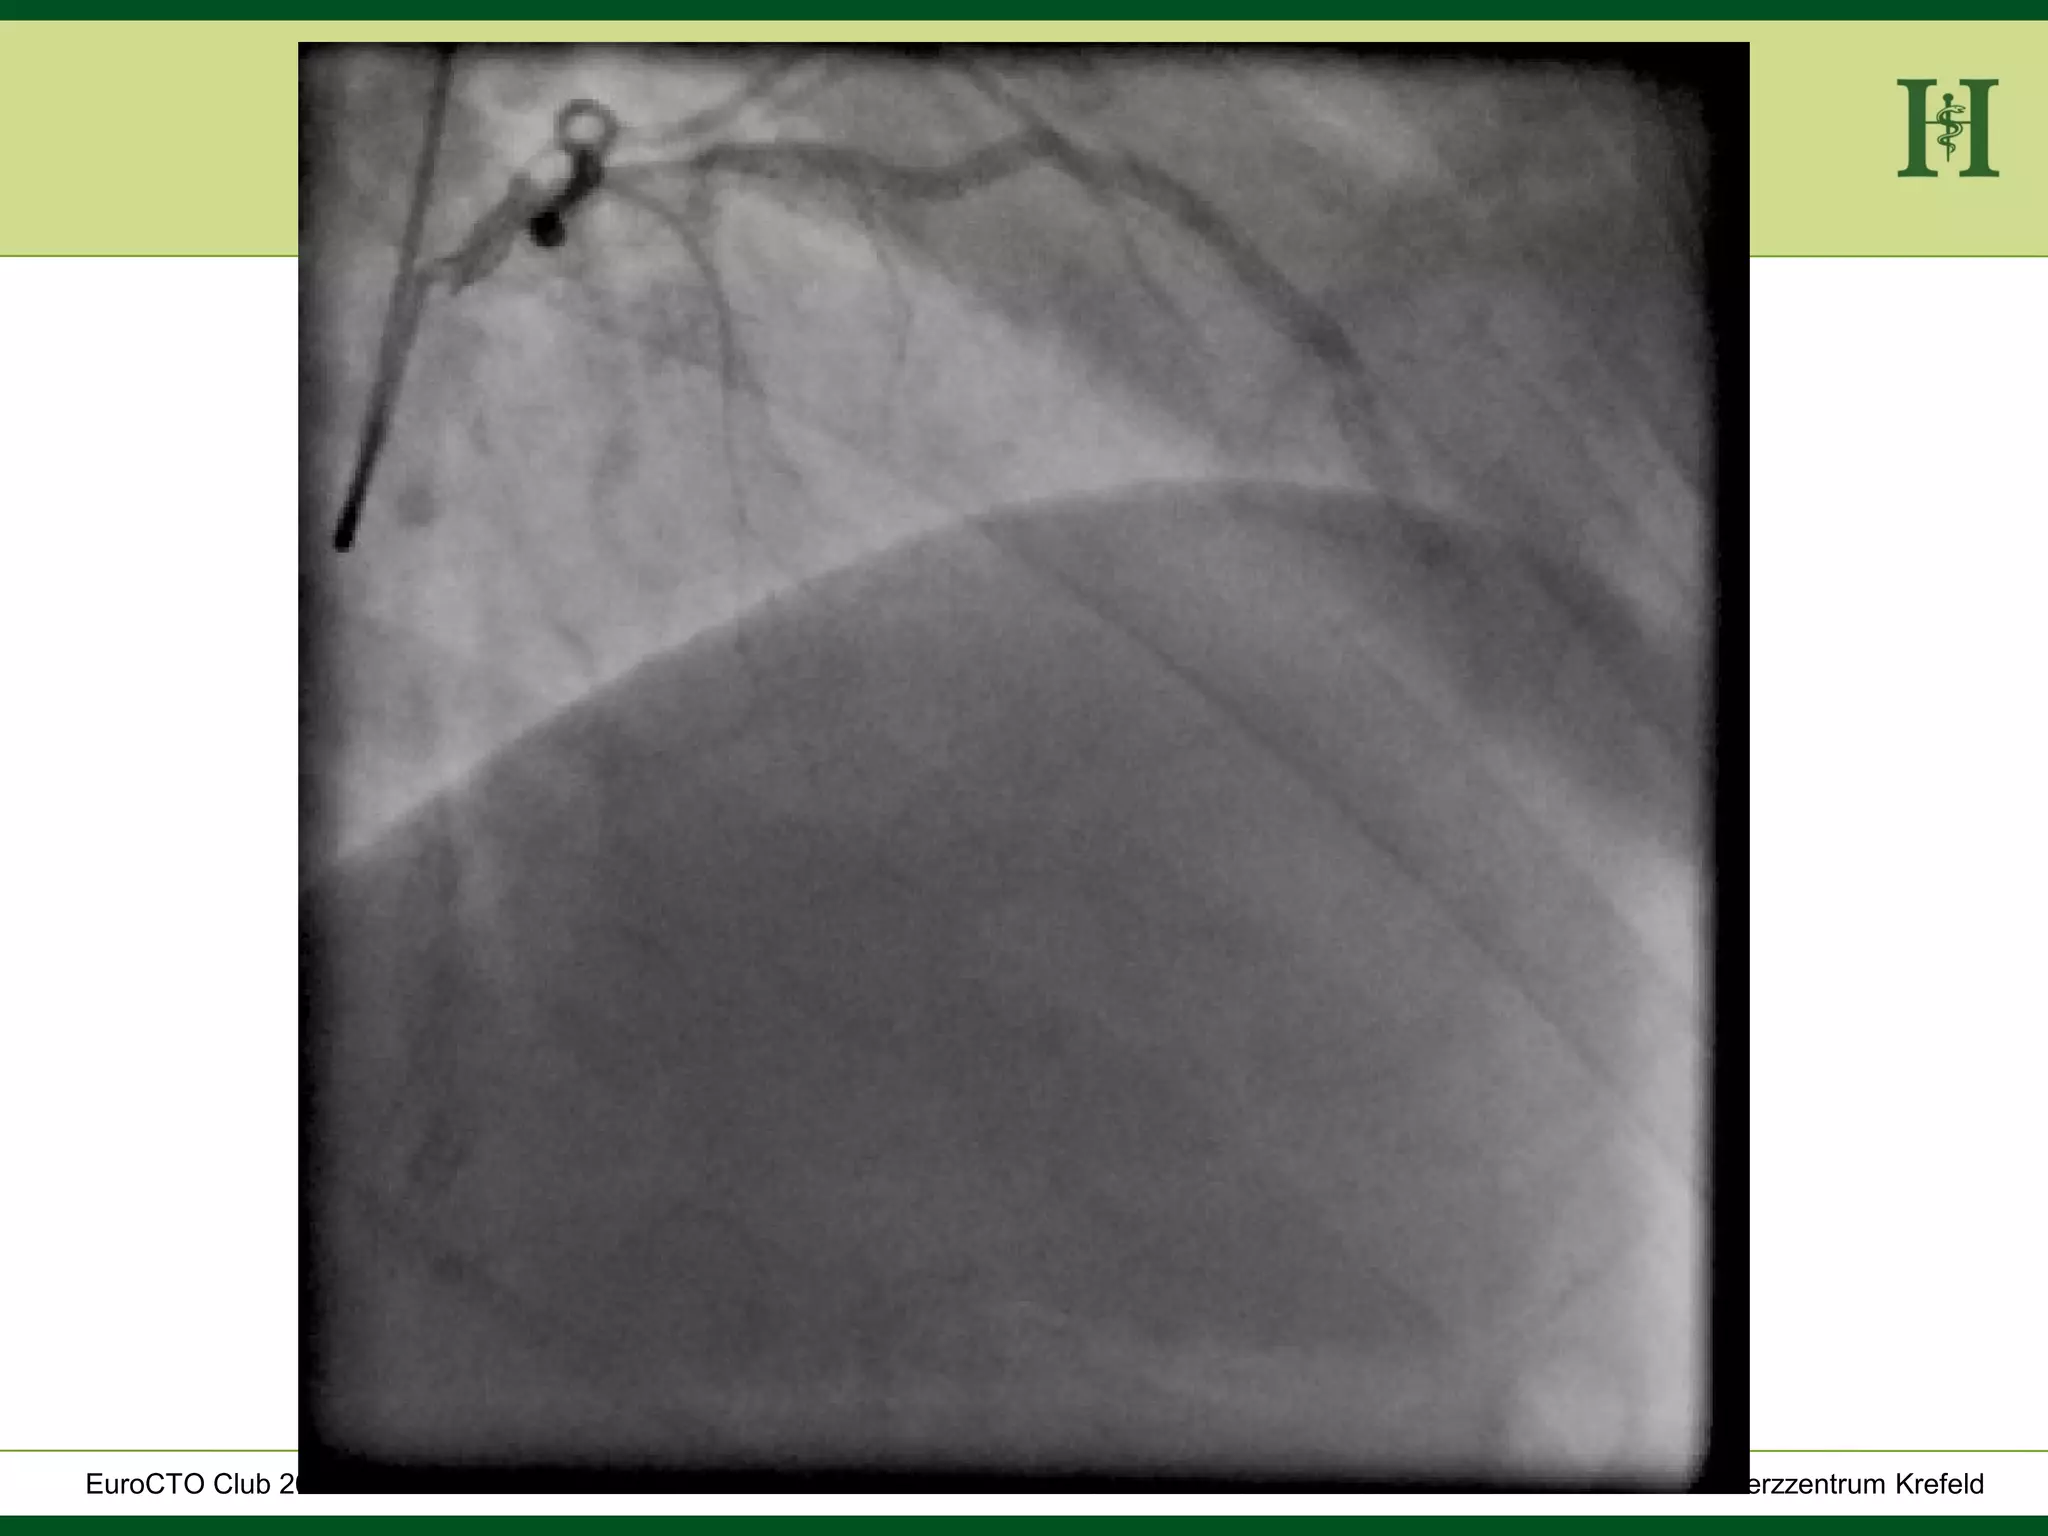

Proximal

Stent

Stent in

PLD